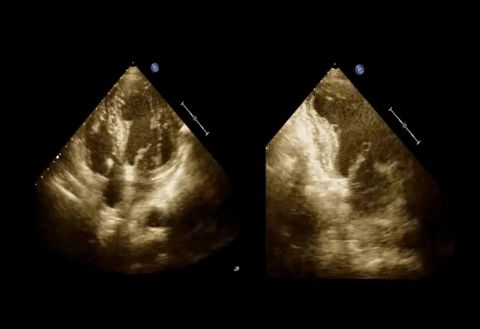

prof. dr hab. n. med. Jarosław KasprzakDane kliniczne:Pacjentka z niewydolnością sercaRozpoznanie główne:Kardiomiopatia przerostowa z zawężaniem drogi odpływu lewej komoryPoruszane zagadnie...